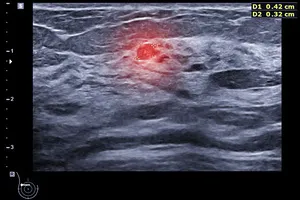

유방 결절은 다양한 원인으로 발생하며, 대부분 양성이지만 일부는 악성일 수 있습니다. 조직검사는 결절의 일부를 채취하여 현미경으로 분석하는 검사입니다.

세침흡인검사보다 굵은 바늘을 이용하여 결절의 조직을 일정량 채취하는 방법입니다. 장점은 세침흡인검사보다 많은 양의 조직을 얻을 수 있어 진단의 정확도가 높습니다. 단점은 세침흡인검사보다 통증이 약간 더 심할 수 있으며, 출혈이나 감염의 위험이 약간 증가할 수 있습니다.